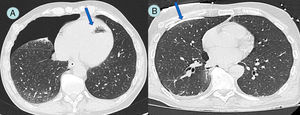

Our patient was a 67-year-old man with a history of perforated colorectal carcinoma, requiring emergency surgery, followed by treatment with chemotherapy and radiation therapy. During the staging CT, a pulmonary nodule measuring 11mm contiguous with the inferior pulmonary vein was observed. Fine needle aspiration biopsy was performed under general anesthesia, and during the procedure pneumothorax and left ventricular air embolism were visualized. This was a tomographic finding, and the patient was asymptomatic when the complication was discovered. A pleural drainage tube was placed, and pulmonary expansion was immediately observed (Fig. 1). Transthoracic echocardiogram was performed, ruling out coronary and/or ventricular complications. A waiting approach was taken, with echocardiographic studies and hemodynamic monitoring, which remained within normal values. A follow-up CT was performed after 48h, showing reabsorption of the intracardiac air. The patient progressed without problems and was discharged on day 4 after the procedure.